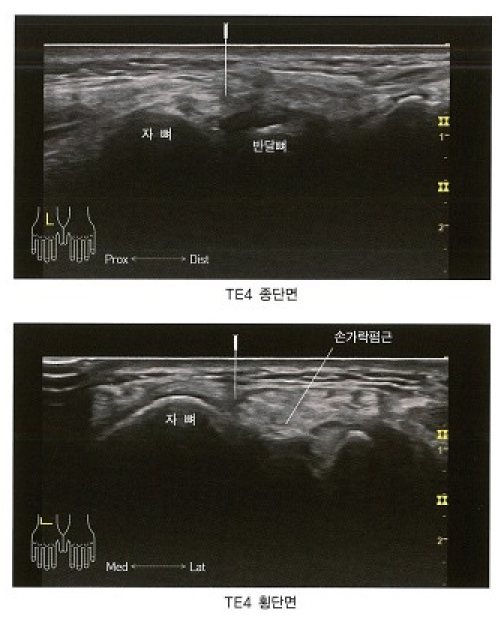

꼼꼼하게 진찰해본 결과 한의학적으로 습비증(濕痺)으로 진단되었는데, 특히 담적이 많은 체질이신 분들은 결절종이 재발하는 경향이 있습니다. 양방과 다르게 한의학적으로 진단하고 치료하기 때문에 접근 방법이 다릅니다. 잘 낫지 않는 결절종은 한의학적 관점에서 접근해볼 필요가 있습니다. > 경혈 초음파 습비증으로 진단한 뒤 민감한 압통이 나타나는 수소양삼초경의 양지(陽池, TE4)혈자리를 촉진하고 그 자리에 프로브를 대어 초음파 영상으로 관찰해보았습니다. 아래 그림은 경혈학 교과서에 실린 양지혈의 표준 CT 및 초음파 영상입니다. 손등 쪽 손목주름 위, 손가락폄근힘줄(ED)의 척골측 오목한 곳에 위치하는데요.

대학경락경혈학실습, 대전대학교 한의과대학 경락경혈학교실 양지혈의 표준 초음파 영상과 비교하여 차이는 없는지 살펴보았습니다.